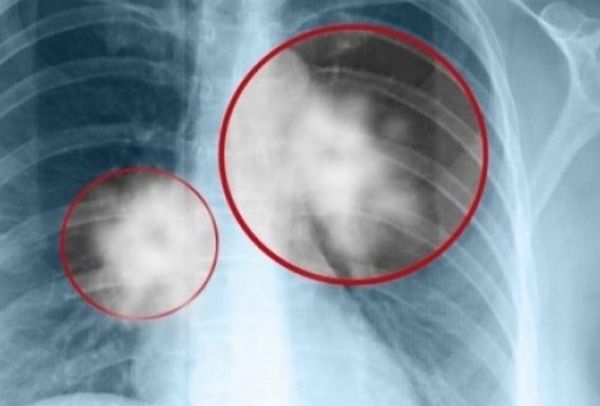

Στο Κέντρο Μοριακής Ανοσολογίας (CIM) στην Κούβα διατίθεται δωρεάν, το πρώτο εμβόλιο στους ασθενείς με καρκίνο του πνεύμονα. Σύμφωνα με τους ειδικούς είναι μια νέα θεραπεία, μοναδική στον κόσμο, η οποία μπορεί να σταματήσει την εξέλιξη της νόσου, χωρίς να επηρεάζει την ποιότητα ζωής των ανθρώπων.

«Τα αποτελέσματα του εμβολίου δίνουν ένα ποσοστό επιβίωσης των ασθενών, ο όγκος δεν εξαλείφεται, αλλά σταματά να αναπτύσσεται, επιτρέποντας στους ασθενείς να ζουν περισσότερο και ιδιαίτερα με μια καλή ποιότητα ζωής, οι παρενέργειες είναι ελάχιστες», λέει η γιατρός Arlhee Diaz.